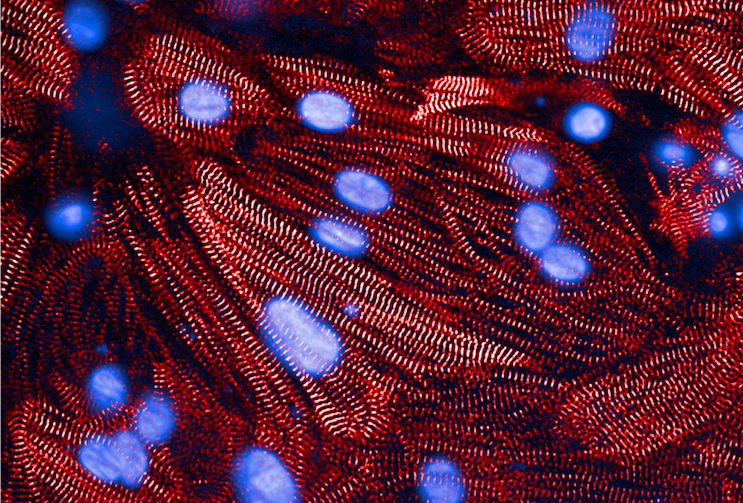

A microscope image of heart muscle cells, with contraction-related proteins stained red and cell nuclei stained blue.

Credit: Anant Chopra, Broad/Bayer Precision Cardiology Lab

Heart muscle cells

Laboratory experiments reinforced the mechanistic pathway: When researchers reduced CD36 protein expression in cultured heart muscle cells using RNA interference, the cells took up less fuel and showed impaired contraction.